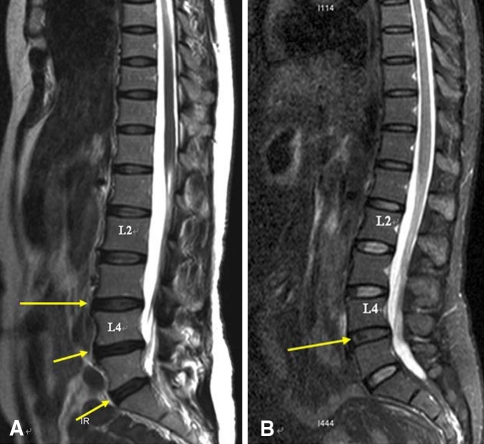

An example of the application of such grading system of the lumbar spine in a 50-year-old non-yoga office lady and a 51-year-old yoga teacher is illustrated in Fig. 2.

Fig. 2.

a Sagittal MRI of the lumbar spine of a 50-year-old female office lady without yoga experience. Findings: Grade III disc (an inhomogeneous disc with unclear distinction between nucleus and annulus) at L3–4 intervertebral disc (long arrow). Grade IV disc (an inhomogeneous hypointense disc with decreased height) at L4–5 and L5–S1 intervertebral discs (short arrows). b Sagittal MRI of the lumbar disc of a 51-year-old yoga teacher with 15 years of teaching experience. Findings: Grade III disc (an inhomogeneous disc with unclear distinction between nucleus and annulus) at L4–5 intervertebral disc (long arrow)